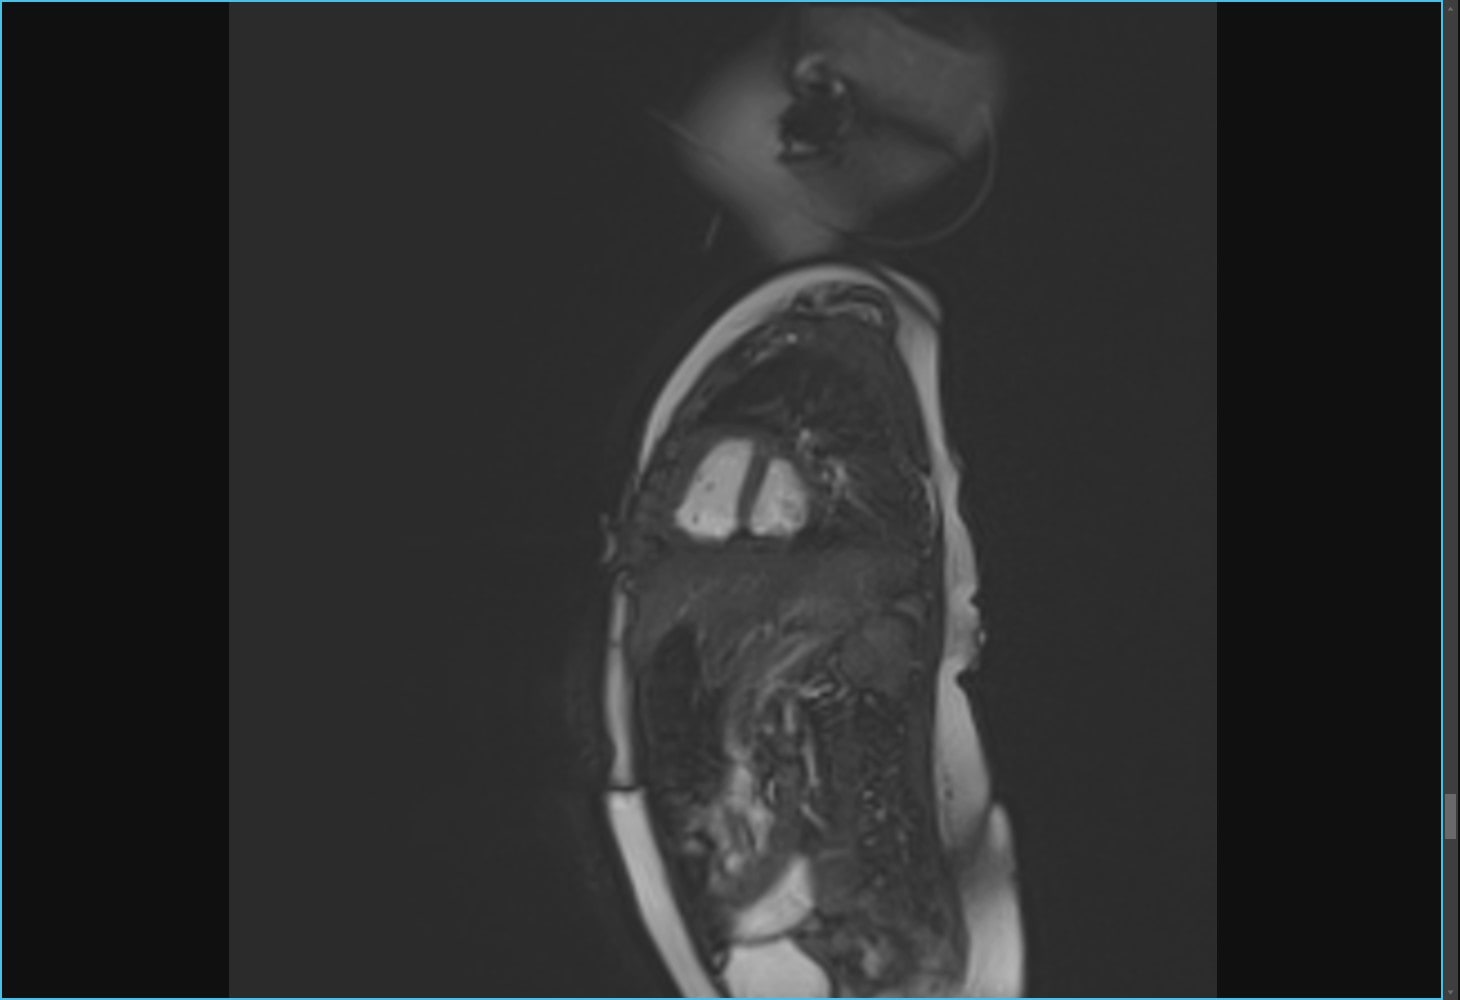

生まれつき心臓の機能に障害がある疾患を先天性心疾患と呼称します。従来は小児科の病気として考えられていた先天性心疾患ですが、近年は治療技術の発達、内科治療の進歩により、多くのお子さんが思春期、成人期まで到達することが可能になっています。このように、先天性心疾患は成人循環器疾患の一分野となりつつあり、現在成人期に達している患者における先天性心疾患手術はかならずしも根治していない例が多く、長期間にわたり心血管形態や機能を繰り返し評価することになるため、折々の患者さんの容態に合わせた診断技術、特に非侵襲的な検査法の必要性が高まっています。榊󠄀󠄀󠄀󠄀󠄀󠄀原記念病院のMRI装置は、呼吸停止をすることなく、体格や胸郭変形にかかわらず、視野の制限なく再現性の高い画像を取得することができますから、複雑な体静脈または肺静脈奇形、大静脈肺動脈吻合、単心室や右心室の形態評価だけでなく、機能評価においても優れた診断能を有します。

乳児(4カ月)の自由呼吸下MRI